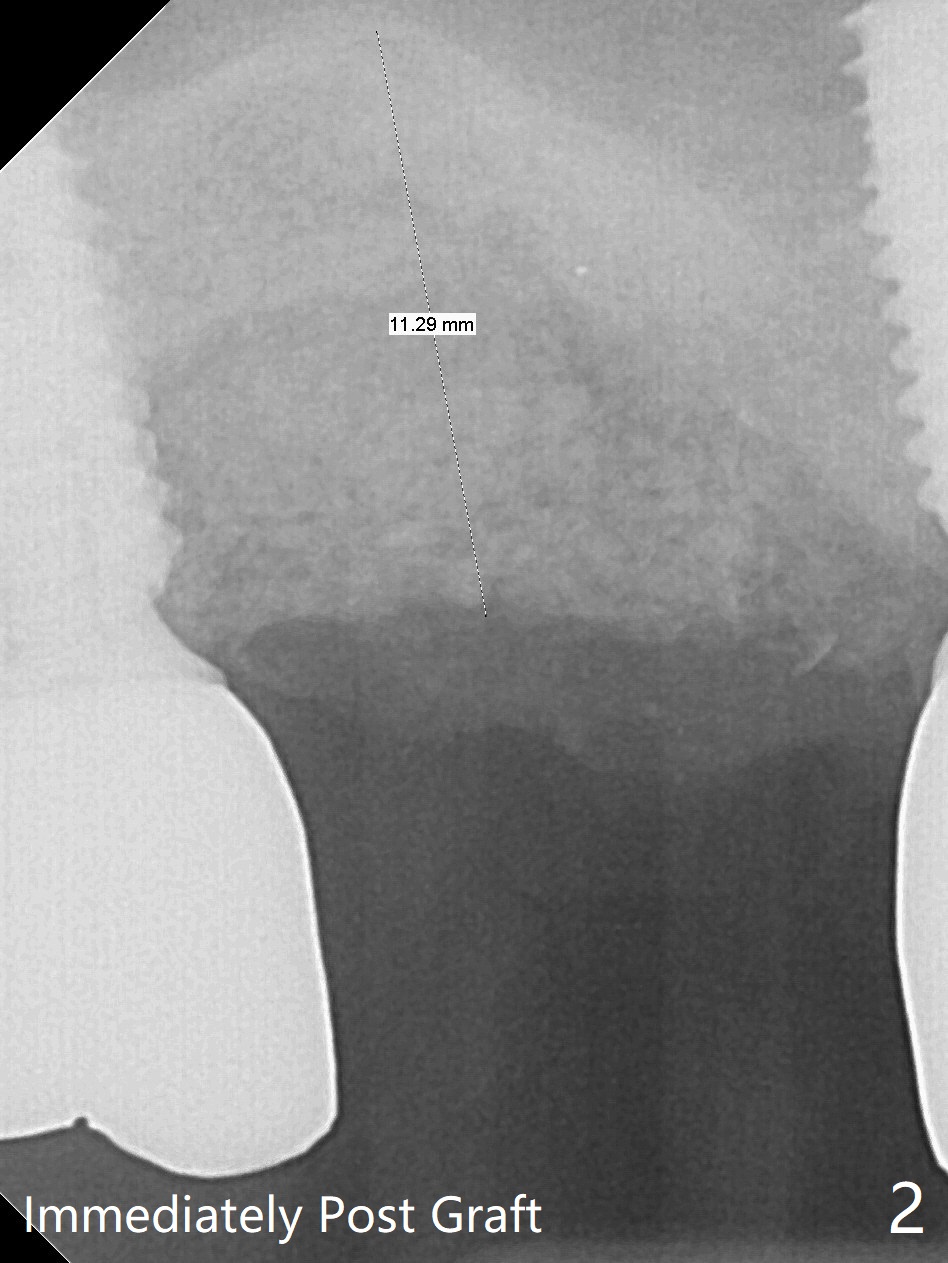

Removal of the implant at #2 is extremely difficult because of fusion of the abutment with the implant.  Buccal and palatal incisions are made to remove the bone buccomesiodistal to the implant.  After implant removal, the exposed mesial coronal implant threads at #1 are cleaned with Titanium brush; allograft is placed against the exposed threads (Fig.1 *), followed by 2 pieces of PRF membrane and 6-month collagen membrane.  Periodontal dressing is applied after suturing.  Partially due to traumatic implant removal and partially due to easy and repeated loss of periodontal dressing, bone height reduces nearly 4 months postop (compare Fig.2,3).  More discouraging is the invasion of loose nonkeratinized buccal gingiva into the healed socket nearly 4 months post graft (Fig.4 N).  Tissue punch thorough a guide should expose the implant site to the nonkeratinized tissue.  Can we fabricate a guide with buccal clearance underneath so that a flap can be raised buccally, i.e., to push the palatal keratinized tissue buccally?